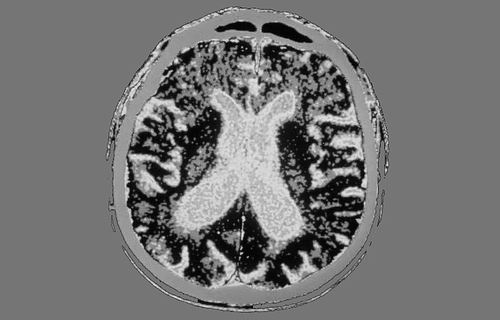

作为安全试验的一部分,数百万干细胞被注射到帕金森病患者的大脑中。图片来源:GJLP

为了检验帕金森病细胞疗法的安全性和潜在副作用,日本京都大学的研究人员进行了一项Ⅰ/Ⅱ期临床试验。7名年龄50~69岁的患者接受了来自人诱导多能干细胞的多巴胺能前体细胞移植,区域为双侧大脑。在研究持续的24个月中,没有报告严重副作用,移植的细胞产生了多巴胺,且没有过度生长或形成肿瘤。

在另一项单独的I期临床试验中,美国纪念斯隆-凯特琳癌症中心的Viviane Tabar和同事研究了来自人胚胎干细胞的多巴胺能前体细胞产品——bemdaneprocel的安全性。年龄中位数为67岁的12名患者通过手术移植该前体细胞到双侧大脑壳核。5名患者接受了低剂量(每侧壳核90万细胞),7名接受了高剂量(每侧壳核270万细胞)。这些细胞产品的耐受普遍良好,在后续18个月中没有报告与疗法相关的严重副作用,且没有出现运动障碍的迹象。此外,在低剂量和高剂量组均观察到一些运动功能的改善。